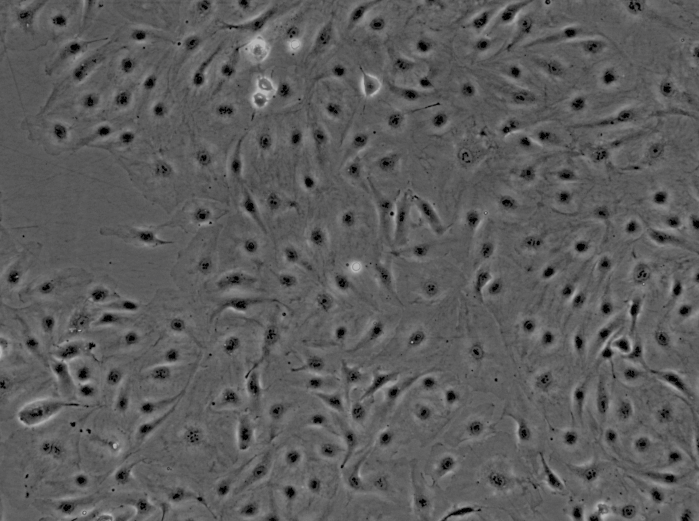

来自ScienCell研究实验室的HPAEC从人肺动脉中分离出来。HPAEC在*代冷冻保存并冷冻。每个小瓶含有>5×10^5个细胞,1ml体积。HPAEC的特征在于用对vWF /因子VIII和CD31(PECAM)特异的抗体的免疫荧光,以及通过摄取DiI-Ac-LDL。HPAEC对HIV-1,HBV,HCV,支原体,细菌,酵母和真菌均为阴性。在ScienCell研究实验室提供的条件下,HPAEC保证进一步扩大15次人口倍增。

肺动脉携带从心脏到肺部的脱氧血液。与其他血管内皮细胞相似,肺动脉内皮细胞(PAEC)通过产生两种过程的激活剂和抑制剂来调节凝血和纤维蛋白溶解。此外,PAEC产生影响血小板粘附和聚集的介质[1]。PAEC还通过合成和处理血管活性分子来控制血管张力[2]。PAEC进一步与间充质细胞相互作用并调节炎症事件[3,4]。PAEC的这些功能涉及急性肺损伤,肺动脉高压,水肿,栓塞,肺动脉动脉瘤和慢性阻塞性肺病。